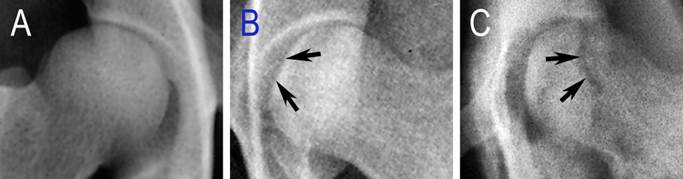

Three weeks after the operation, six animals underwent X-ray examination. All of the operated femoral heads showed a different extent of inhomogeneous changes, and four of them showed several osteopenic areas (Figure 5B, blue arrows), which were accompanied with sclerotic rims (Figure 5B, white arrows). But, all of these changes were not obvious. At 6 weeks, two of the six operated femoral heads demonstrated mild segmental flattening (Figure 6B, black arrows). One animal developed a femoral head fracture (Figure 6C) on the experimental side. At 9 weeks, two of the operated femoral heads showed joint space narrowing with secondary osteoarthritis.

Figure 5

General changes seen in radiographic images. A: the anteroposterior X-ray examination of the hip; B: the experimental femoral head (blue arrows: osteopenic areas; white arrows: sclerotic rims); C: the control femoral head.

Figure 6

Specific changes seen in radiographic images. A: the control femoral head of control lateral; B: mild flattening of the articular cartilage (black arrows); C: a fractured femoral head (black arrows).